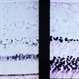

- Condition/keywords

- retinal ischemia

- This patient with long standing diabetes has peripheral non-perfusion.